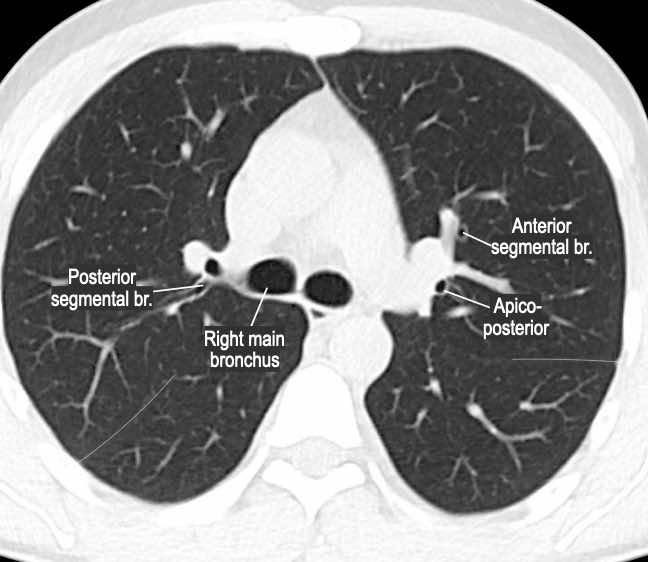

Phế quản trên CT

Cuộn qua các hình ảnh để quan sát khí quản phân chia thành phế quản chính phải và trái, sau đó tiếp tục phân chia thành các phế quản thùy và phế quản phân thùy.